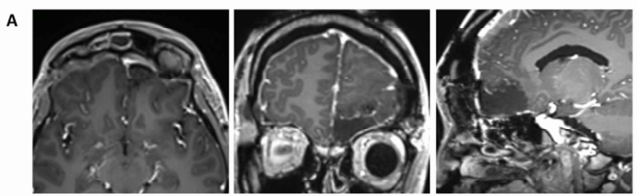

然而,5个月后再次复查MRI,发现肿瘤体积再次显著增大,病变已累及筛窦及额叶实质(图1D)。

图1D:第二次活检后5个月,病灶再次增大

手术不能再等,2014年10月我接受手术治疗。手术台上,医生们发现这个病灶硬得像石头,但好在医生帮我把脑子里的病变全部切除。

术中行双侧额部冠状切口,采用额下入路。病灶质地极硬,与周围炎性纤维化组织分界清晰,可完整分离,外观酷似曲霉性肉芽肿;遂行病灶全切除。受累硬膜附着区予电凝并彻底清理。因术中冰冻切片未见恶性证据,且无需肿瘤学意义上的扩大切除,筛窦结构予以保留完整。术后MRI(图2A)示颅内病灶已全切,但嗅球周围仍有持续强化灶。

图2A:术后MRI示额部肉芽肿已完整切除